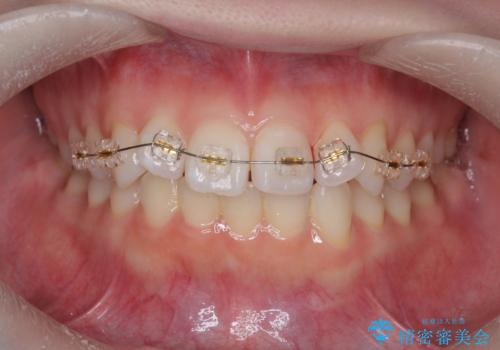

- 矯正装置

- インビザライン +部分ワイヤー矯正

- 出っ歯に見える前歯、捻れてしまった小臼歯の改善を求めて来院されました。

マウスピースでは改善の難しい小臼歯のねじれをまず部分ワイヤー矯正で改善し、その後マウスピース矯正で前歯の突出感を改善します。